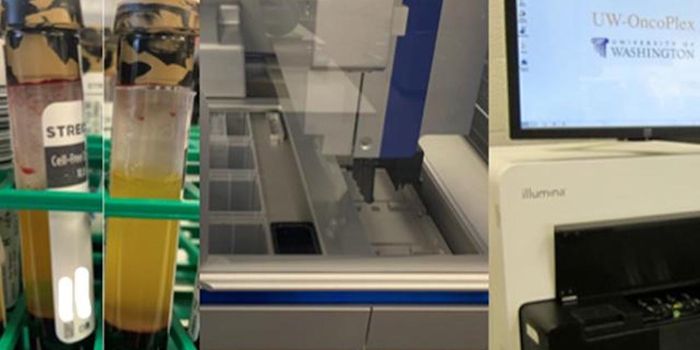

APR 26, 2022Clinical & Molecular DXAs cancer cells grow and divide, their DNA is released into the bloodstream. This DNA, called ctDNA (circulating ...